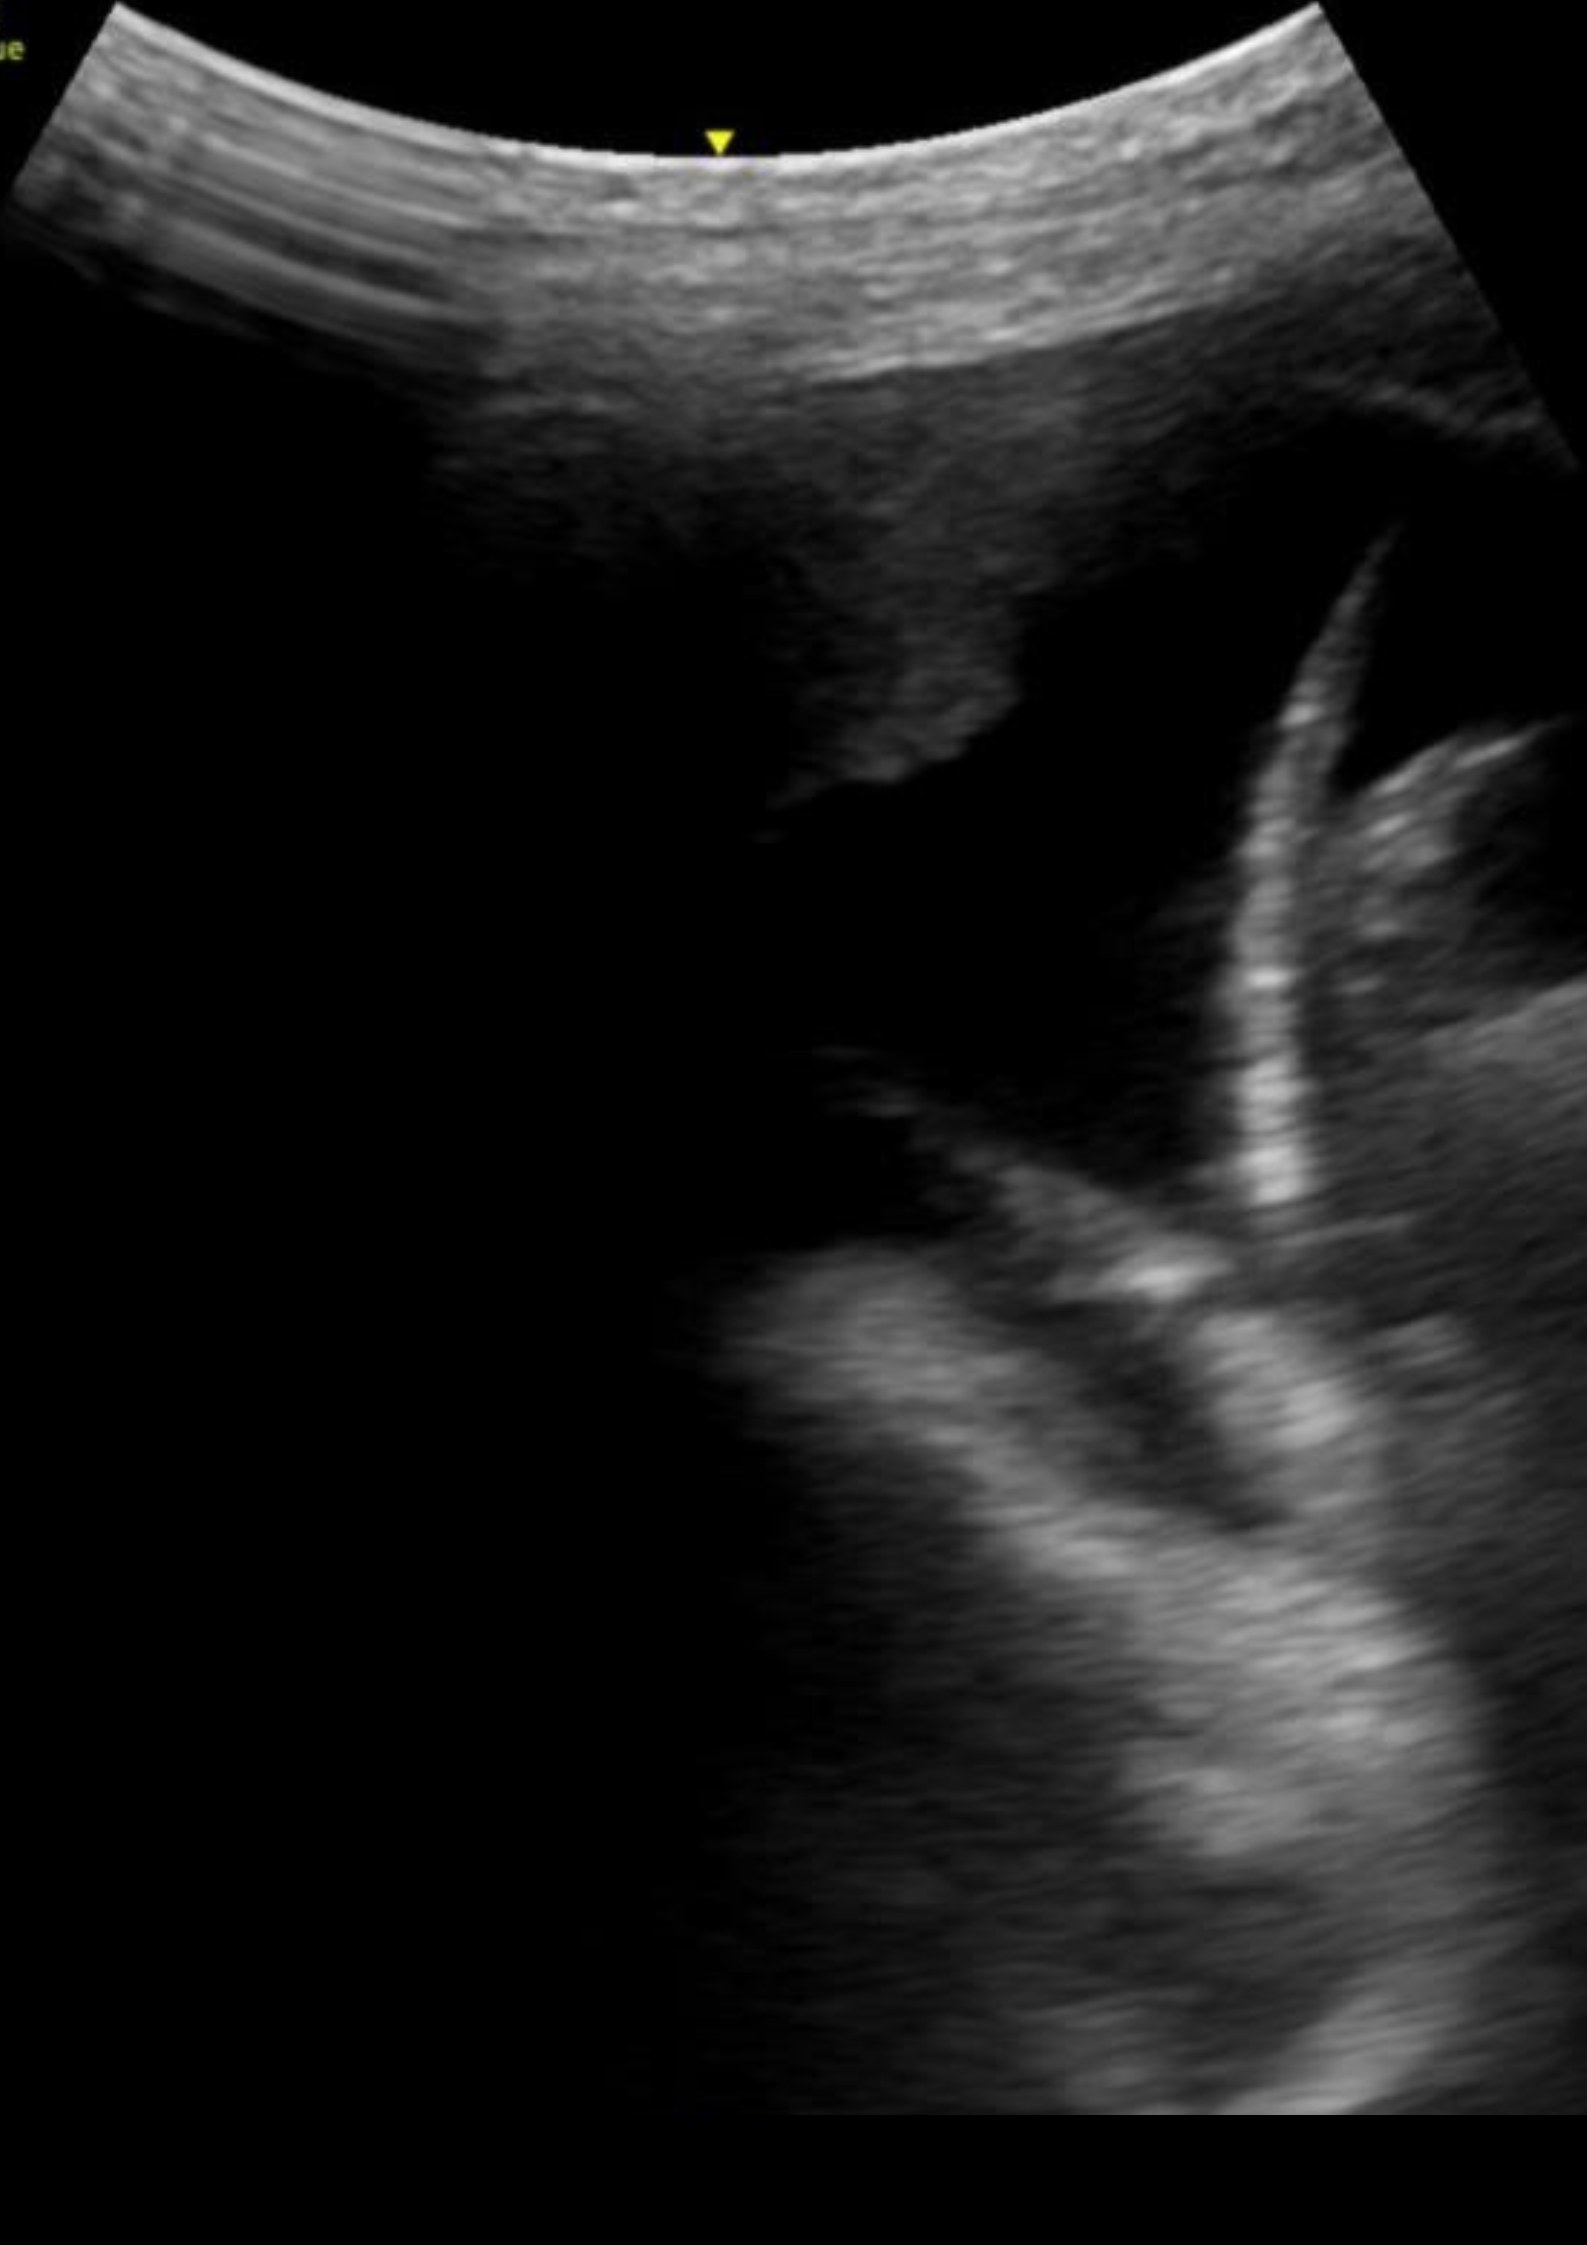

Hallazgos ecográficos

En la ecografía pulmonar observamos varios patrones de líneas B bilaterales de predominio derecho, con hallazgo de consolidación en punto PLAPS (posterolateral alveolar and/or pleural syndrome) y derrame pleural.

La ecografía pulmonar en Atención Primaria no está tan establecida como en el caso de Urgencias, sin embargo, un correcto manejo de la misma permite diferenciar entre diferentes motivos de disnea como son la descompensación cardíaca y el broncoespasmo, así como patología infecciosa. El punto PLAPS, situado en la parte postero-inferior-lateral del pulmón, es el punto más rentable para el diagnostico de las consolidaciones pulmonares así como el derrame pleural, independientemente de la posición del paciente.